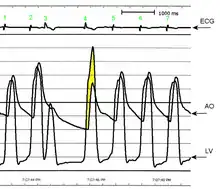

AO = Descending aorta; LV = Left ventricle; ECG = Electrocardiogram.

After the third QRS complex, the ventricle has more time to fill. Since there is more time to fill, the left ventricle will have more volume at the end of diastole (increased preload). Due to the Frank–Starling law of the heart, the contraction of the left ventricle (and pressure generated by the left ventricle) will be greater on the subsequent beat (beat #4 in this picture). Because of the dynamic nature of the outflow obstruction in HCM, the obstruction increases more than the left ventricular pressure increase. This causes a fall in the aortic pressure as the left ventricular pressure rises (seen as the yellow shaded area in the picture).

Upon cardiac catheterization, catheters can be placed in the left ventricle and the ascending aorta, to measure the pressure difference between these structures. In normal individuals, during ventricular systole, the pressure in the ascending aorta and the left ventricle will equalize, and the aortic valve is open. In individuals with aortic stenosis or with HCM with an outflow tract gradient, there will be a pressure gradient (difference) between the left ventricle and the aorta, with the left ventricular pressure higher than the aortic pressure. This gradient represents the degree of obstruction that has to be overcome in order to eject blood from the left ventricle.

The Brockenbrough–Braunwald–Morrow sign is observed in individuals with HCM with outflow tract gradient. This sign can be used to differentiate HCM from aortic stenosis. In individuals with aortic stenosis, after a premature ventricular contraction (PVC), the following ventricular contraction will be more forceful, and the pressure generated in the left ventricle will be higher. Because of the fixed obstruction that the stenotic aortic valve represents, the post-PVC ascending aortic pressure will increase as well. In individuals with HCM, however, the degree of obstruction will increase more than the force of contraction will increase in the post-PVC beat. The result of this is that the left ventricular pressure increases and the ascending aortic pressure decreases, with an increase in the LVOT gradient.

While the Brockenbrough–Braunwald–Morrow sign is most dramatically demonstrated using simultaneous intra-cardiac and intra-aortic catheters, it can be seen on routine physical examination as a decrease in the pulse pressure in the post-PVC beat in individuals with HCM.